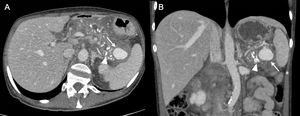

A 50-year-old man with a previous history of chronic pancreatitis had an episode of exacerbation. Axial (A) and coronal (B) CT angiography reconstructions of the abdomen and pelvis in the arterial phase show a pseudoaneurysm of the splenic artery (arrow) adjacent to the tail of the pancreas and close to the splenic hilum. The pancreas shows numerous calcifications (arrowhead) as a sign of chronic pancreatitis.

50-year-old man who came in with arterial hypotension, fever and pain in the right hypochondriac region. Blood tests showed increased acute phase reactants. With clinical suspicion of complicated biliary colic, ultrasound of the abdomen and pelvis (A) showed signs of acute calculous cholecystitis and, when colour Doppler was applied, a structure with the "yin-yang" sign was detected in the hepatic hilum (arrow). Sagittal maximum intensity projection reconstruction of the arterial phase CT angiography (B) confirms a pseudoaneurysm of the right hepatic artery (arrow). It progressed to haemorrhagic cholecystitis and urgent embolization of the pseudoaneurysm was performed.